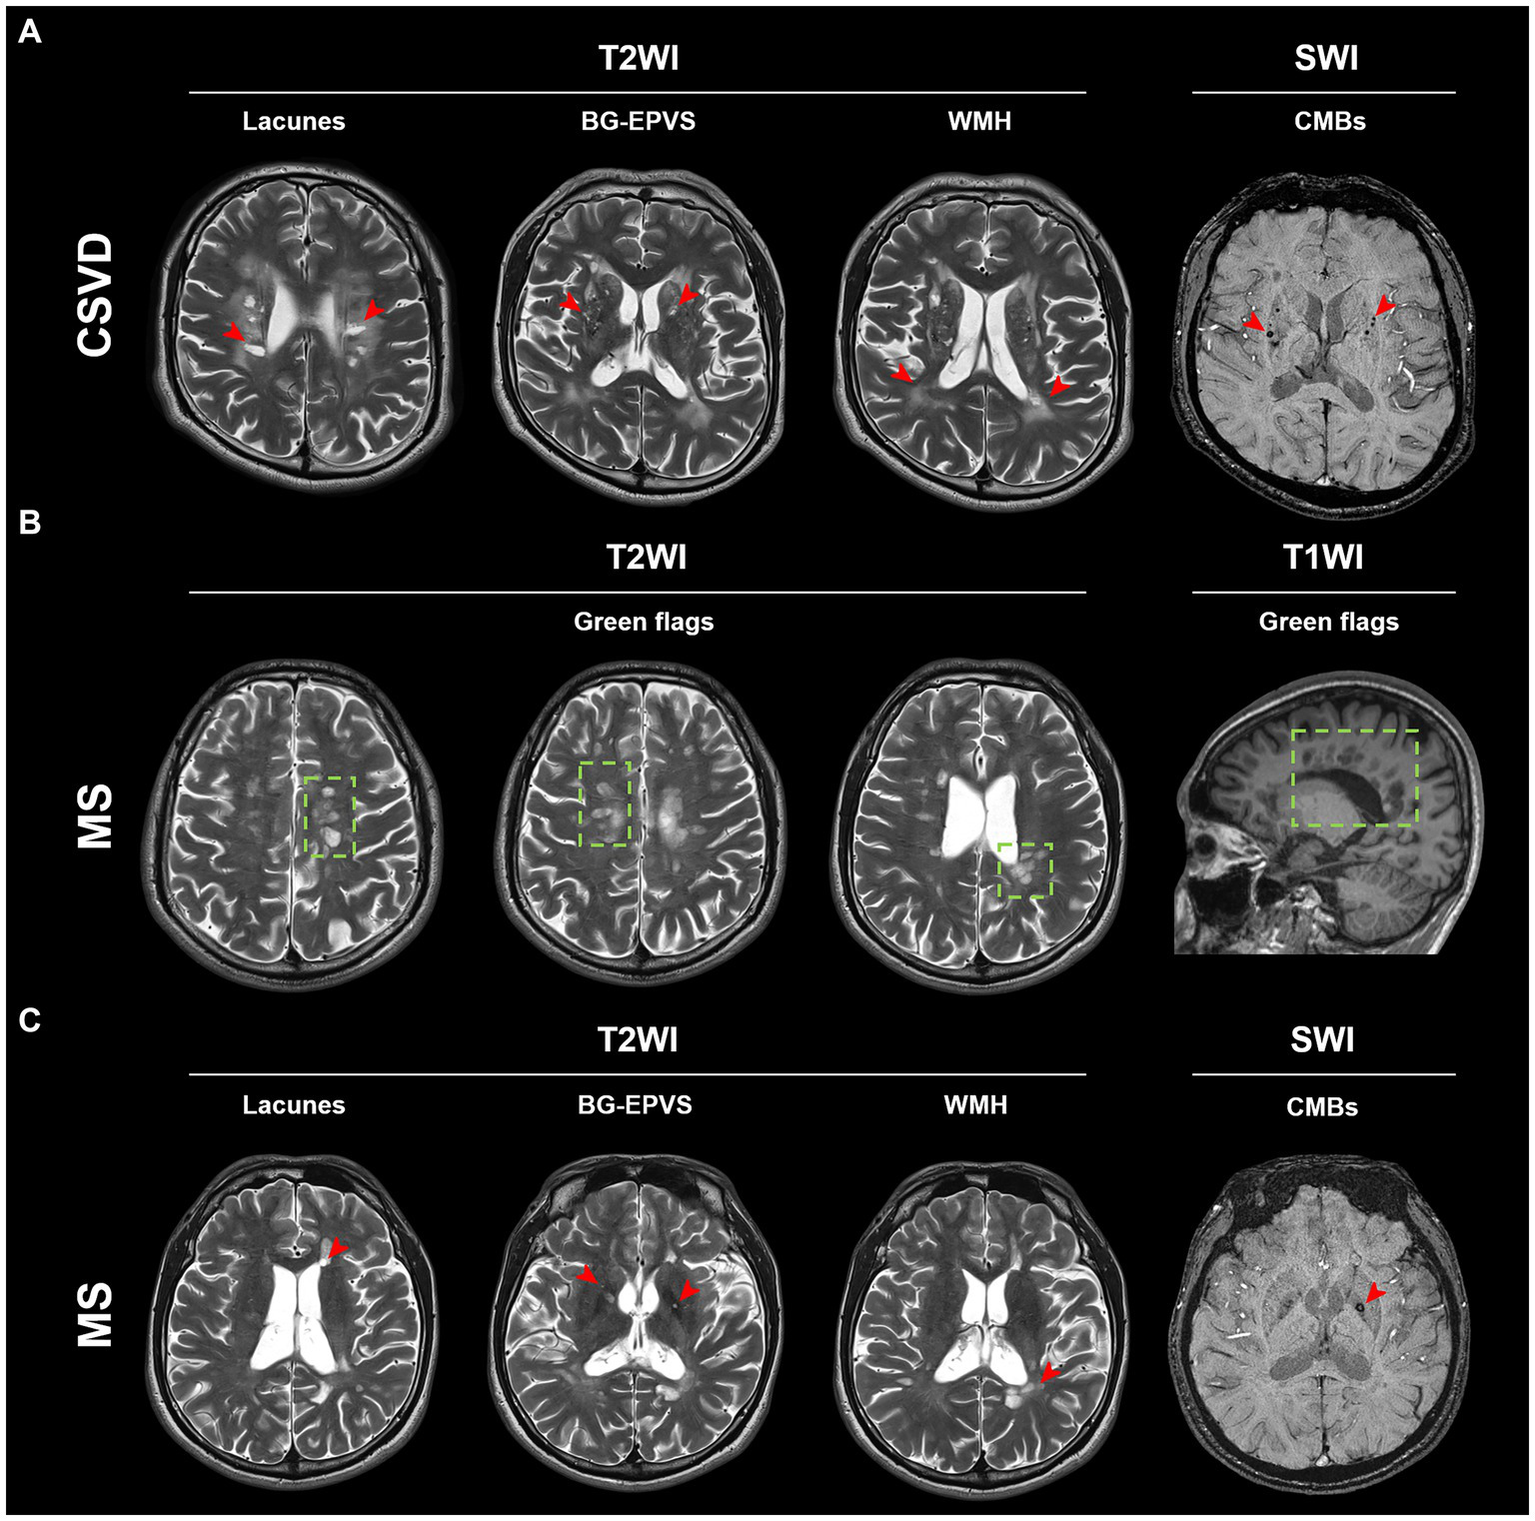

Although the aforementioned MRI imaging features were prevalent in CSVD patients (Figure 2A), some MS patients also showed similar imaging features (Figures 2B,C). This makes it challenging to discriminate between MS and CSVD on MRI. We found that PRL was present in more than half of the cases in the subgroup of MS patients with CSVD imaging features (Table 3). However, there were no significant differences in CSVD imaging features between MS patients with and without PRL (Supplementary Table S1).

Figure 2

Typical MRI imaging features of MS and CSVD. (A) Typical lesions of lacunes, BG-EPVS, WMH, and CMBs (red arrow) in a CSVD patient. (B) Typical green flags in an MS patient. Green flags: periventricular lesions suggestive of multiple sclerosis; or periventricular lesions perpendicular to the corpus callosum (“Dawson’s fingers”). (C) Lacunes, BG-EPVS, WMH, and CMBs (red arrow) can also be found in this MS patient. BG-EPVS, Enlarged perivascular spaces (EPVS) in the basal ganglia; WMH, White matter hyperintensity; CMBs, Cerebral microbleeds; MS, Multiple sclerosis; and CSVD, Cerebral small vessel disease.